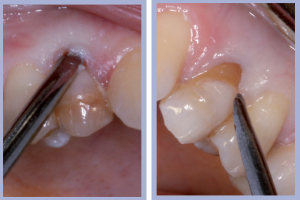

- Figg. 7a, b – Toilette chirurgica

- Figg. 8a, b – Mappatura alveolare tramite sonda parodontale

– Sondaggio alveolare e revisione chirurgica (Figg. 7-8);